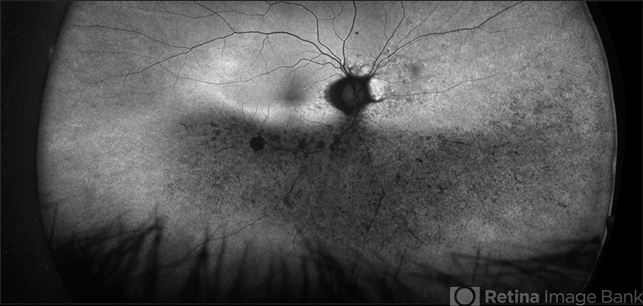

- A 60-year-old Caucasian female presented with reduced night vision and constricted visual fields. The fundus exam revealed pigmentary changes in the peripheral retina. Fundus autofluorescence depicted the schematic appearance of a Phoenix , with the hypo-autofluorescence corresponding to the head and wings of the phoenix. Genetic testing was positive for a heterozygous RHO mutation